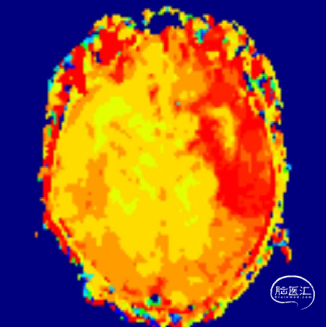

术后即刻影像。

支架植入后造影提示残余狭窄约10%。术中患者生命体征稳定,术后患者恢复良好出院,继续抗血小板聚集及他汀类药物治疗。